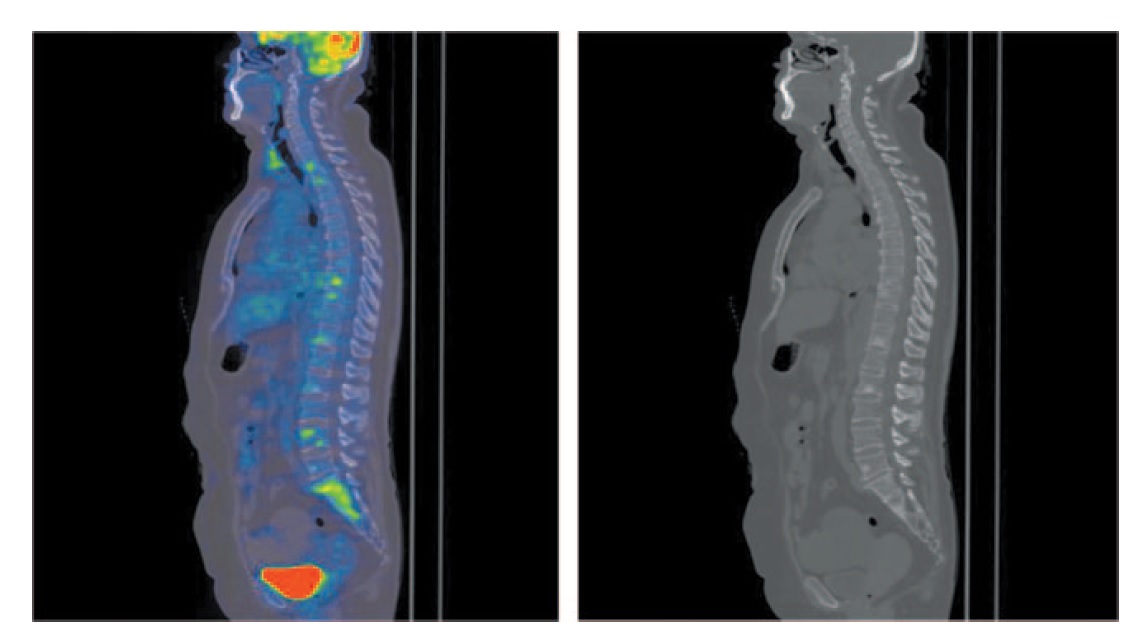

На MIP ПЭТ/КТ и аксиальных проекциях отмечается диффузное умеренное увеличение размеров щитовидной железы с повышенной фиксацией 18-ФДГ, коэффициент стандартизированного максимального накопления 18-ФДГ SUVmax составил 10,90. Структура ее однородная. С двух сторон отмечаются шейные лимфоузлы размером 8–13 мм с повышенной фиксацией радиофармпрепарата (РФП); рис. 1.

Рис. 1. Больная Б., 72 года, до лечения. На MIP и аксиальных ПЭТ/КТ проекциях отмечается диффузное умеренное увеличение размеров щитовидной железы: правой доли до 10×21 мм, левой доли до 13×22 мм с повышенной фиксацией РФП, SUVmax 10,90. Структура ее в условиях нативного сканирования однородная. Определяются лимфатические узлы с двух сторон размером до 8 мм SUVmax 5,48; IIa, IIb группы справа и III, IV групп с двух сторон размером до 13 мм с повышенной фиксацией РФП, SUVmax 12,93. / Fig. 1. A 72-year-old woman before the treatment. MIP and axial positron emission tomography/computed tomography (PET/CT) images show moderate diffuse enlargement of the thyroid gland: the right lobe of the thyroid gland is 10×21 mm, the left lobe of the thyroid gland is 13´22 mm with increased uptake of radiopharmaceutical, SUVmax 10.90. The structure of the thyroid gland during native computed tomography images was homogeneous. The images showed lymph nodes on both sides measuring 8 mm SUVmax 5.48; IIa, IIb groups on the right side and III, IV groups on both sides measuring 13 mm with increased uptake of radiopharmaceutical (RFP), SUVmax 12.93.